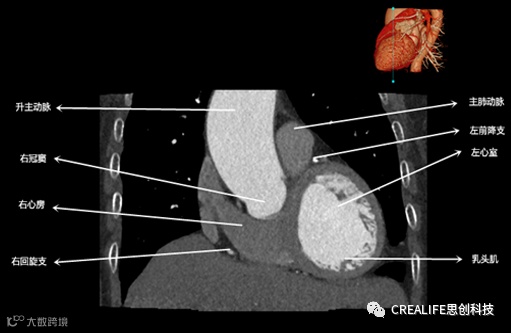

今天,跟大家分享心脏影像的经典层面——冠状位。通过冠状位的影像,我们可以从正位观察到心脏结构,看到主动脉的纵向剖面及冠窦交界处的心脏形态等多方位的心脏结构。现在,就让我们率先一睹“冠状位”的奇妙风采吧!

毋庸置疑,影像解剖学可为医师提供优良的诊断依据,包括瓣膜钙化程度、主动脉瓣环直径、主动脉窦直径及高度、冠状动脉开口高度、入径血管直径等关键数据,以此,为术前提供更全面的评估指标。